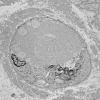

16A Normal nerve, Node of Ranvier EM 1 - Copy